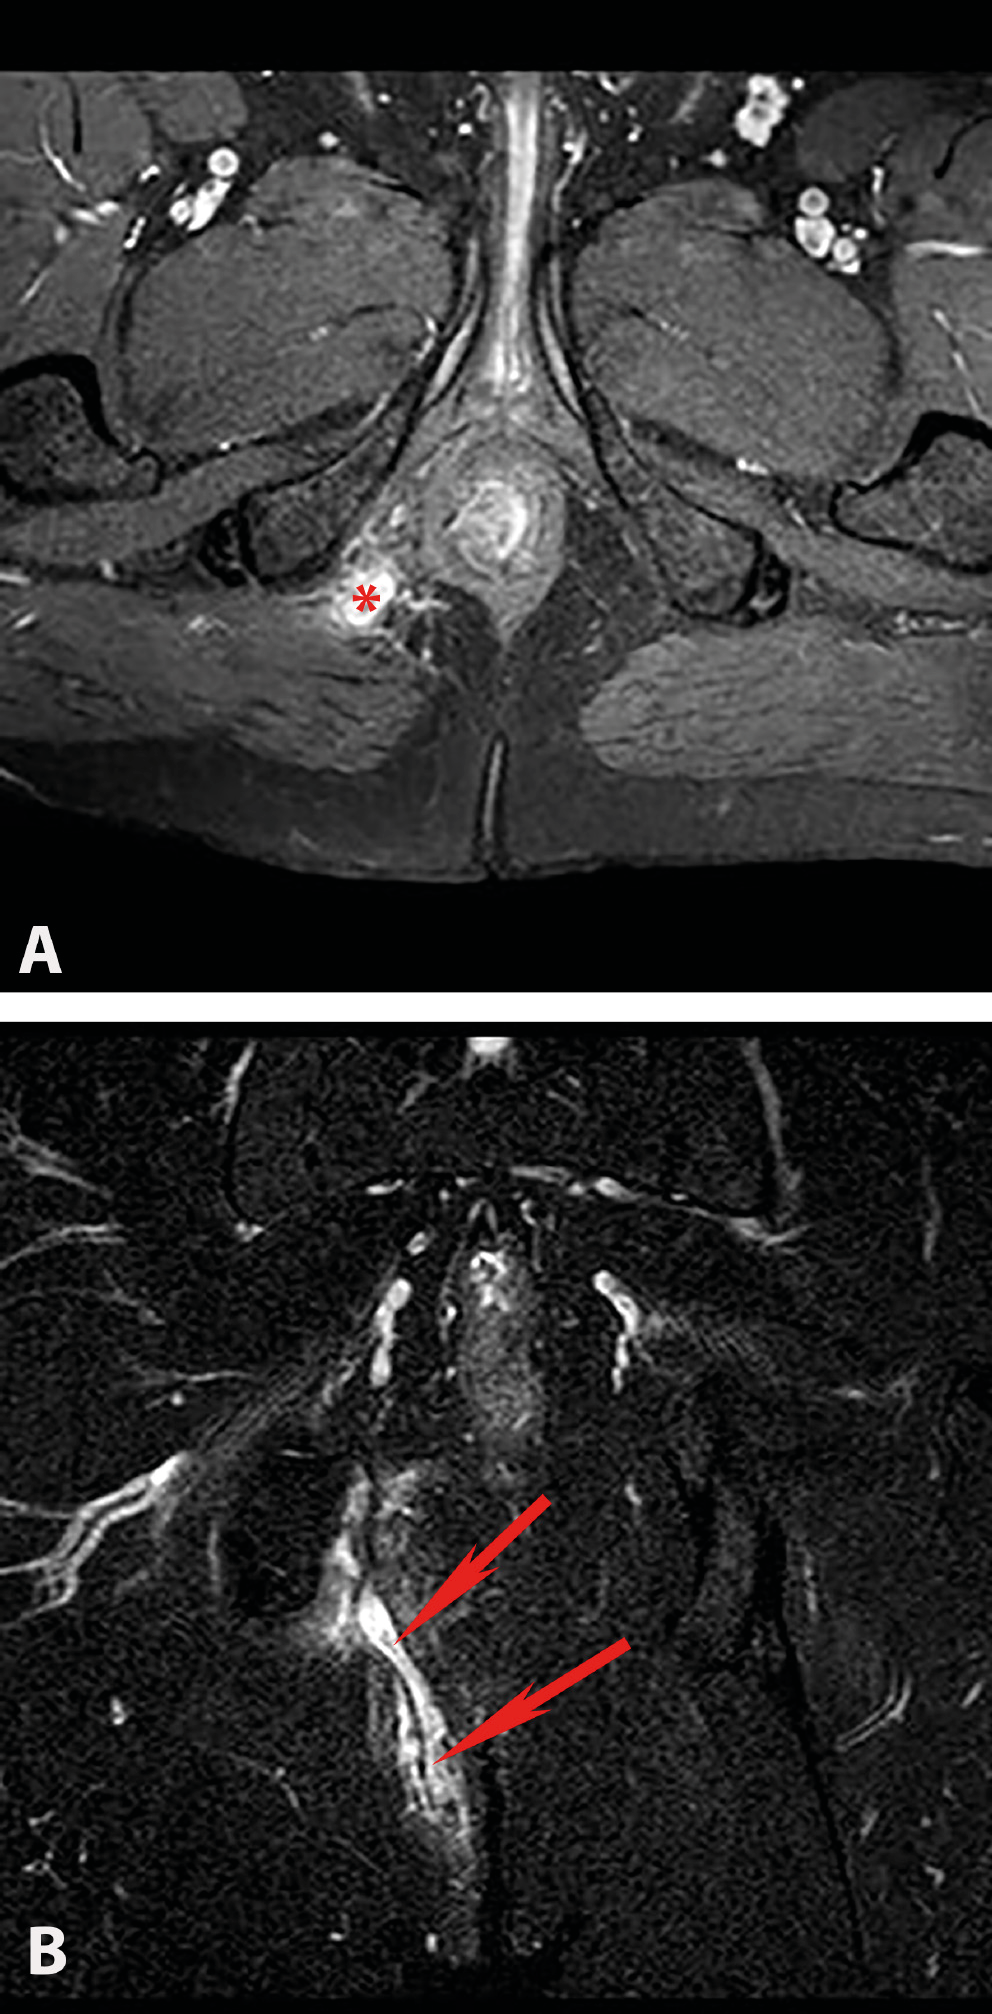

Of the 114 patients included in the study, 78 had complex chronic anal fistulas, and 36 had anorectal abscesses accompanied by anal fistulas. As a result of the MRIs performed in the anorectal abscess group, perianal abscesses were detected in 14 (58%) patients (Figure 2A,B), ischiorectal abscesses in 6 (25%) patients (Figure 3A,B) and intersphincteric abscesses in 4 (17%) patients (Figure 4). Suprasphincteric fistulas were observed in 3 patients, extrasphincteric fistulas were found in 2 patients, horseshoe fistulas were present in 2 patients (Figure 5A,B), and transsphincteric fistulas were observed in the remaining patients with complex fistulas. Thirteen patients had 2 external fistula ora and 4 patients had 3 external fistula ora. Eight patients in the fistula group had an abscess pouch associated with the fistula tract. These findings are consistent with the literature.